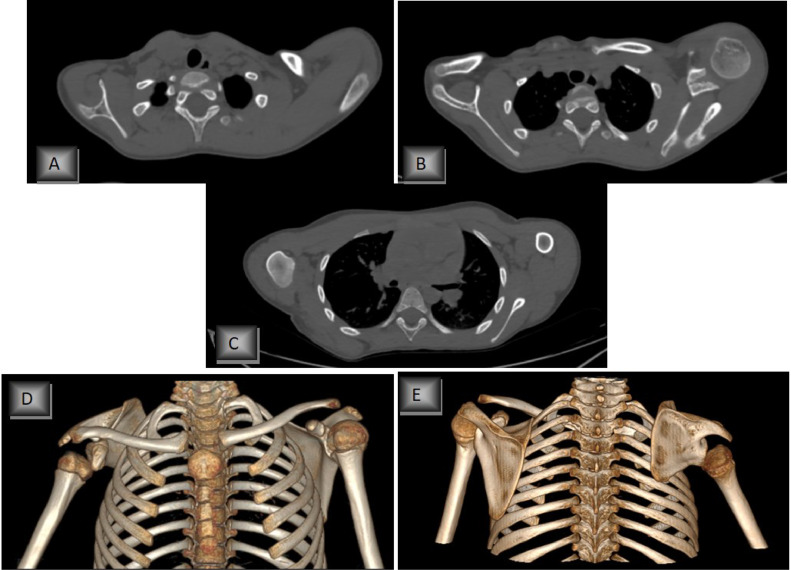

We present the case of a 19-year-old male presented with a deformity of the right shoulder. The right scapula was found to be raised and fixed medially on physical examination. There was partially restricted movement of the shoulder joint. The patient had not previously undergone shoulder X-rays; 3 dimensional computed tomography (3D CT) examination was requested right away, which revealed abnormality, anterior curving of the supraspinous portion of the raised right scapula (Fig. 1). The horizontal and vertical lengths were almost the same in both scapulas. There was no omovertebral bone.

Fig. 1.

(A, B, C) axial sections, (D, E) and 3D reconstruction chest CT scan, (A) shows increased horizontal/vertical length of the right scapula. There is no omovertebral bony connection.